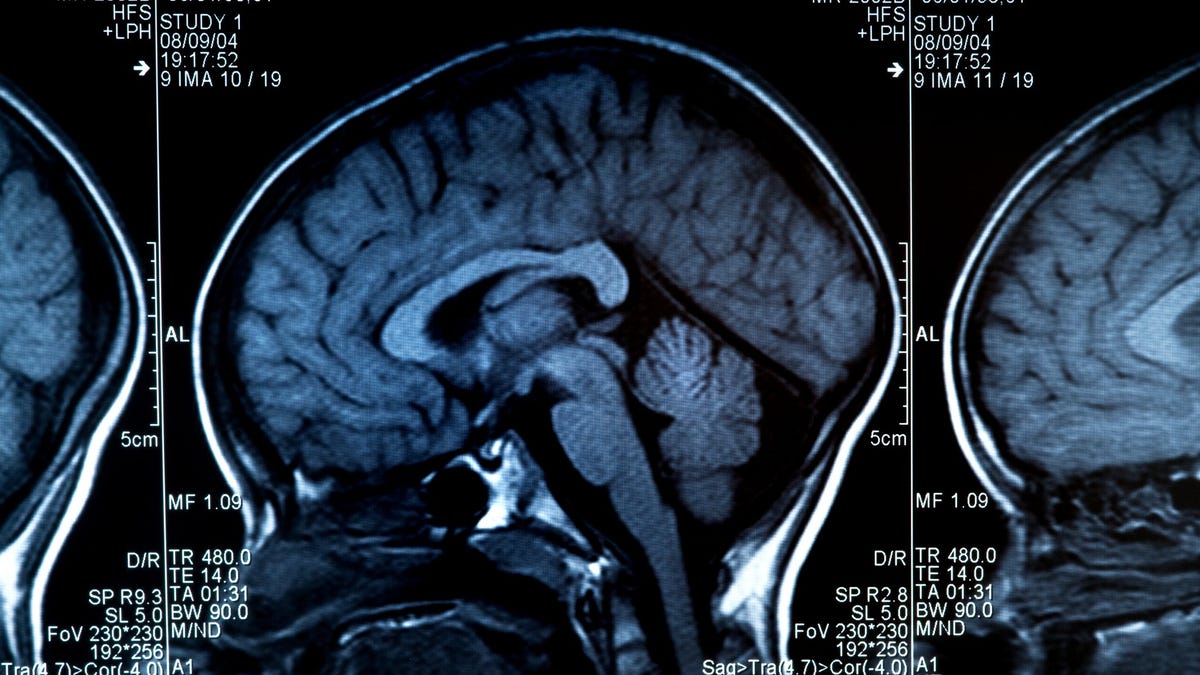

New research published in Science Advances reveals that viruses like SARS-CoV-2 can cause fusion between neurons, leading to ongoing problems in the brain. The study provides insights into the neuropathological mechanisms underlying viral brain infections and their impact on neuronal circuitry and function. The researchers found that SARS-CoV-2 can infect neurons and cause fusion between neighboring cells, resulting in the formation of multinucleated syncytia. This fusion allows the virus to spread within the neurons without release into the extracellular space, potentially leading to permanent alterations in neuronal circuitry and function. The findings suggest that viral infections can cause neurons to malfunction, representing a new neuropathological mechanism with implications for the development of treatments and interventions for viral brain infections.